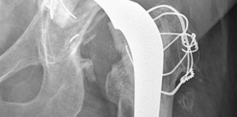

16. Trochanteric osteotomy repaired using a plate, cerclage cables, and allograft strut.

4. Femur—since the patient had a long-stem cemented femoral component, we elected to perform an extended trochanteric osteotomy to gain access to the cement mantle and to aid in the extraction of the femoral component. We also elected to use a trochanteric plate with several cerclage cables and an allograft strut to augment stability for the revision femoral component. A modular femoral revision component that gave primary diaphyseal fixation was chosen due to severe proximal femoral bone loss secondary to osteolysis.